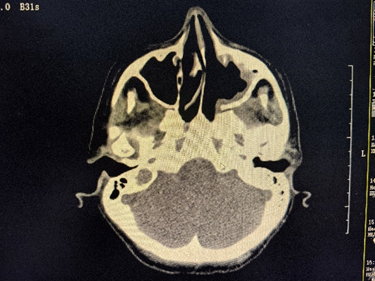

بعد الجولة الأولى من العلاج، خفت حدة احتقان الأنف والنزيف لدى ماكا بشكل ملحوظ، وقل إحساسها بوجود جسم غريب عند البلع بشكل كبير. بعد إكمال الدورة الثانية من العلاج، فوجئت بسرور عندما وجدت أنها تستطيع التنفس من أنفها مرة أخرى، وعادت حاسة الشم لديها إلى طبيعتها! كشف التصوير الشعاعي المتابعة عن انخفاض كبير في حجم الورم في تجويف الأنف والجيوب الأنفية، واستقرت علامات الورم لديها تدريجيًا. تشير جميع هذه العلامات إلى أن خطة العلاج الحالية ناجحة.

△ بعد دورتين من العلاج